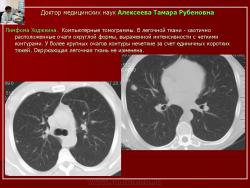

Рис. 12. Б-ной С. Лимфома Ходжкина

Компьютерные томограммы. В легочной ткани - хаотично расположенные очаги округлой формы, выраженной интенсивности с четкими контурами. У более крупных очагов контуры нечеткие за счет единичных коротких тяжей. Окружающая легочная ткань не изменена.

При очаговой форме инвазивного кандидоза, установленной в 38,2% случаев, выявлялись хаотично расположенные интенсивные очаги, размеры которых не превышали 2,0см, более крупные из них имели неоднородную структуру и нечеткие контуры (рис. 12).